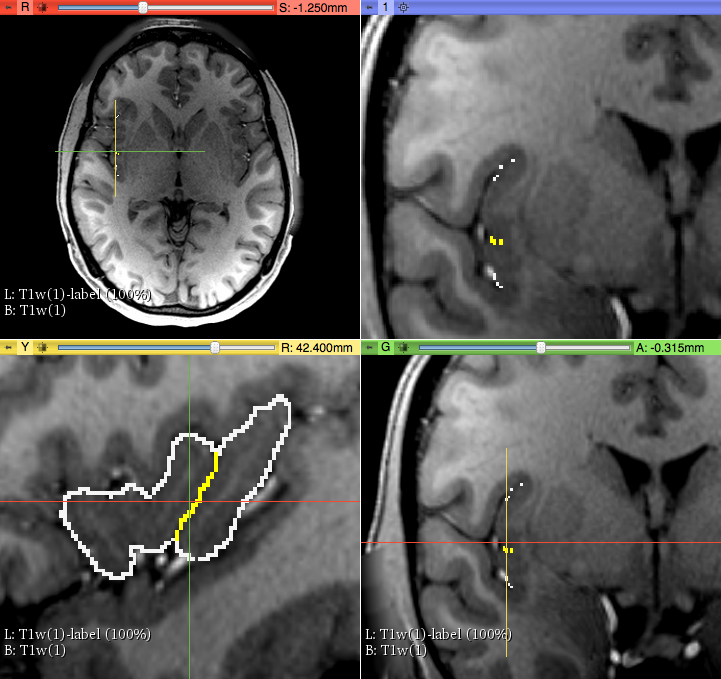

1) On a T1 MRI image, using the Segment Editor module, we used 3 segments (via “add” icon). The first segment was for the background, the second for the whole Insula and the third for the separation between the two subunits of the insula, i.e., aINS and pINS. To establish accurately the borders of aINS and pINS we traced the Circular sulcus and the Central sulcus of the Insula as follows. First, we used three sagittal images where these sulci were visually well-identifiable. Consequently, these sulci were detected on coronal sections as a series of dots, which served as our key anatomical landmarks for the segmentation of aINS and pINS. More specifically, the circular sulcus of the insula determined the outer boarder of the insula in its entirety and the the Central sulcus (cesi) determined the for border between anterior and posterior Insula (coronal view).

2) Using the “Tracing level” tool, we identified the optimal separation border between white and grey matter to obtain the external insular cortex ribbon (i.e., between insula and subarachnoid space). Please note that the part segmented in this step, with the first segment selected, will be the background of the insular cortex, first delineated as a “negative” (unfilled area).

3) Using the “Paint” tool we traced the areas outside of the insular cortex, establishing the “negative” of our target structure.

4) Subsequently, we selected the second segment using “Paint” tool, masking editable area on “Outside all segments”. Then we filled the area by drawing inside the previously obtained negative of the insular cortex. We Repeated this process on each coronal slice where Insula was visible (on average 85 slices with MRI slice thickness 0.7mm).

Circular Sulcus (white) and Central Sulcus (yellow) in the parcellation method of anterior and posterior Insula